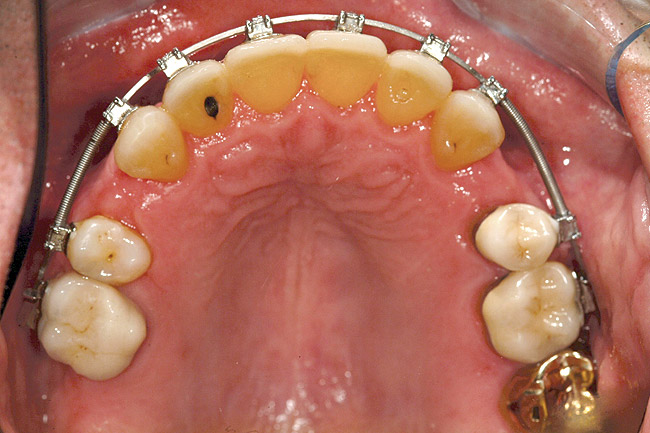

Fig 11. Corticotomy SFOT. A 42-year-old male presented with a history of extraction orthodontic therapy.

Figure 11

Fig 12 (and Fig 13). Incisors were too upright and had severe incisal wear. He was concerned about esthetics of the worn teeth and his insufficient lip support. Progress photo and panorex 9 months after corticotomies were performed on Nos. 6 through 11. Previous extraction sites were reopened orthodontically to improve function and fill lip support. Incisal edges were restored provisionally with composite resin. Note that despite the creation of adequate spaces to replace missing teeth, there is inadequate room for placement of dental implants because of severe tipping of all the anterior teeth. Osteotomy SFOT may have been a better choice because it would have allowed needed alveoloskeletal correction (without excessive tipping) instead of the primarily dentoalveolar correction common in corticotomy SFOT. Restorative dentist: Brad Jones, DDS.

Figure 12

Fig 13 (and Fig 12). Incisors were too upright and had severe incisal wear. He was concerned about esthetics of the worn teeth and his insufficient lip support. Progress photo and panorex 9 months after corticotomies were performed on Nos. 6 through 11.

Figure 13